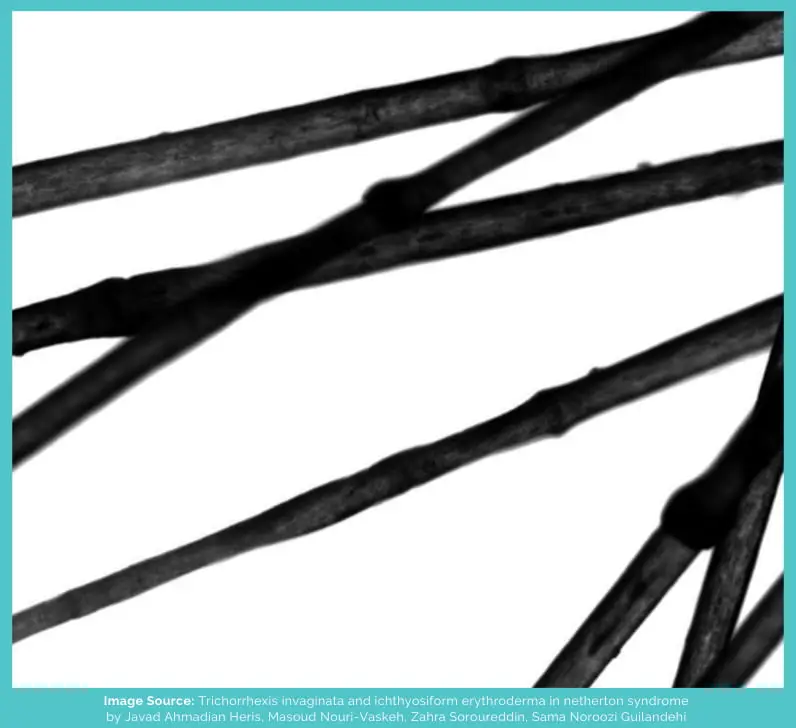

Trichorrhexis invaginata is a hair shaft abnormality in which the distal end (towards the tip) of the hair invaginates (or encloses) around the proximal end (towards the root).

As a result, a ball-and-socket joint-type formation is seen on the hair, and if it breaks from there, it ends up looking like a golf tee (the thing on which the ball is placed in golf).

Because these nodes end up resembling the nodes on a bamboo plant, it’s also known as “bamboo hair.”